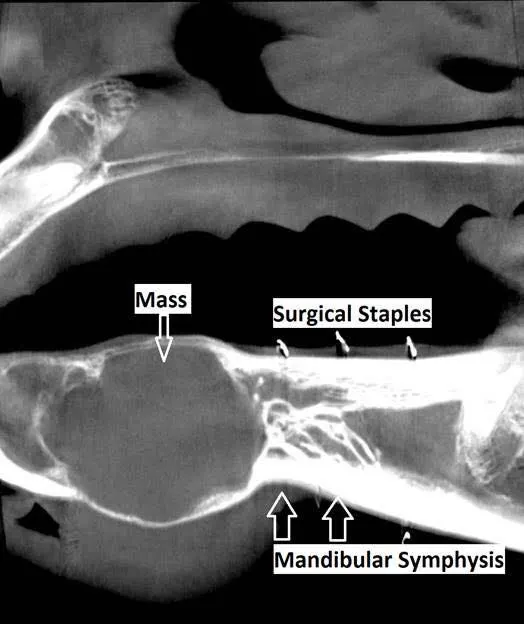

A radiograph revealed that the lump was a tumor. One image showed a round, asymmetrical blob poking up against the bottom gum and dipping far down into the bottom lip. Davis biopsied the mass and ordered a computerized tomography scan that created a three-dimensional view of the jaw, showing the surgery team where the edges of the tumor were.

The mass was an ameloblastic fibroma, a rare type of tumor. Davis said ameloblastic fibroma are unlikely to travel to other parts of the body but are known to grow quickly in their chosen area. The best solution was to remove the tumor by performing a partial mandibulectomy: cutting away part of Nellie’s lower jaw.

The tumor’s position made Nellie a good candidate for surgery. The equine lower jaw is comprised of two hemi-mandibles that join in a V shape at the symphysis, which is the area where the bit lies or the “bars” of the mouth. The mandible continues as one piece in front of the symphysis, and that’s where the horse’s incisors or front teeth are located. Nellie’s tumor didn’t extend beyond the symphysis, so Davis could remove it and leave a small segment of bone joining the two sides. This meant the right and left hemi-mandibles wouldn’t be floating around separately.

While Nellie was under general anesthesia, Davis cut the bone, removed the jaw and the tumor, and rounded off the edges of the mandible remaining in Nellie’s mouth. (Perhaps surprisingly, this type of procedure is often done with the horse standing under sedation, but Davis thought anesthesia was a better option for a sensitive horse.) Then, he stitched together the remaining tissue from her gums.